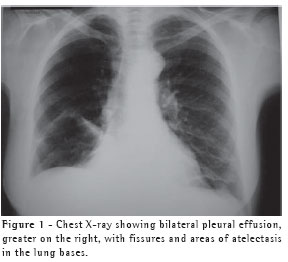

A previously healthy, 63-year-old female who was a nonsmoker and homemaker presented with swelling of the neck, anterior chest wall, abdomen and lower limbs. This was accompanied by discrete dyspnea upon exertion. The symptoms began after light physical activity at a fitness center five days prior. She reported no previous pulmonary disease and was taking 20 mg of fluoxetine per day, 3 mg of bromazepam per day, and regular female hormone replacement. Upon clinical examination, a discrete increase in volume was observed in the left supraclavicular fossa and in the right lateral neck wall. We also observed a diffuse decrease in breath sounds and in vocal fremitus in the lung bases (greater on the right than on the left), as well as edema in the anterior abdominal wall (grade 1) and in the lower limbs (grade 4).We requested the following tests: blood workup, coagulation profile, blood glucose, creatinine, urea, erythrocyte dissemination, total cholesterol, HDL, triglycerides, triiodothyronine, thyroxine, thyroid-stimulating hormone, and partial urinalysis, all of which presented normal results, ruling out dyslipidemia, coagulopathy, infection, nephropathy and hypothyroidism. Radiological evaluation of the thorax revealed slight bilateral pleural effusion (Figure 1), which was confirmed through a computed tomography scan of the chest (Figure 2A). This was complemented with tomography slices acquired at the neck level, revealing edema in the left supraclavicular region with hypodensity (20 × 10 mm) adjacent to the neurovascular bundle of the neck (Figure 2B).

Ultrasound imaging of the cervical region showed the formation of a pocket of cystic fluid collection, posterior to the cervical vessels, suggesting rupture of the left jugular trunk. It also demonstrated a slight increase in the thickness of the left sternocleidomastoid muscle, suggesting an inflammatory process secondary to muscle distention (Figure 3). The patient was submitted to diagnostic thoracentesis on the right side, and the opaque liquid obtained was consistent with chylothorax.